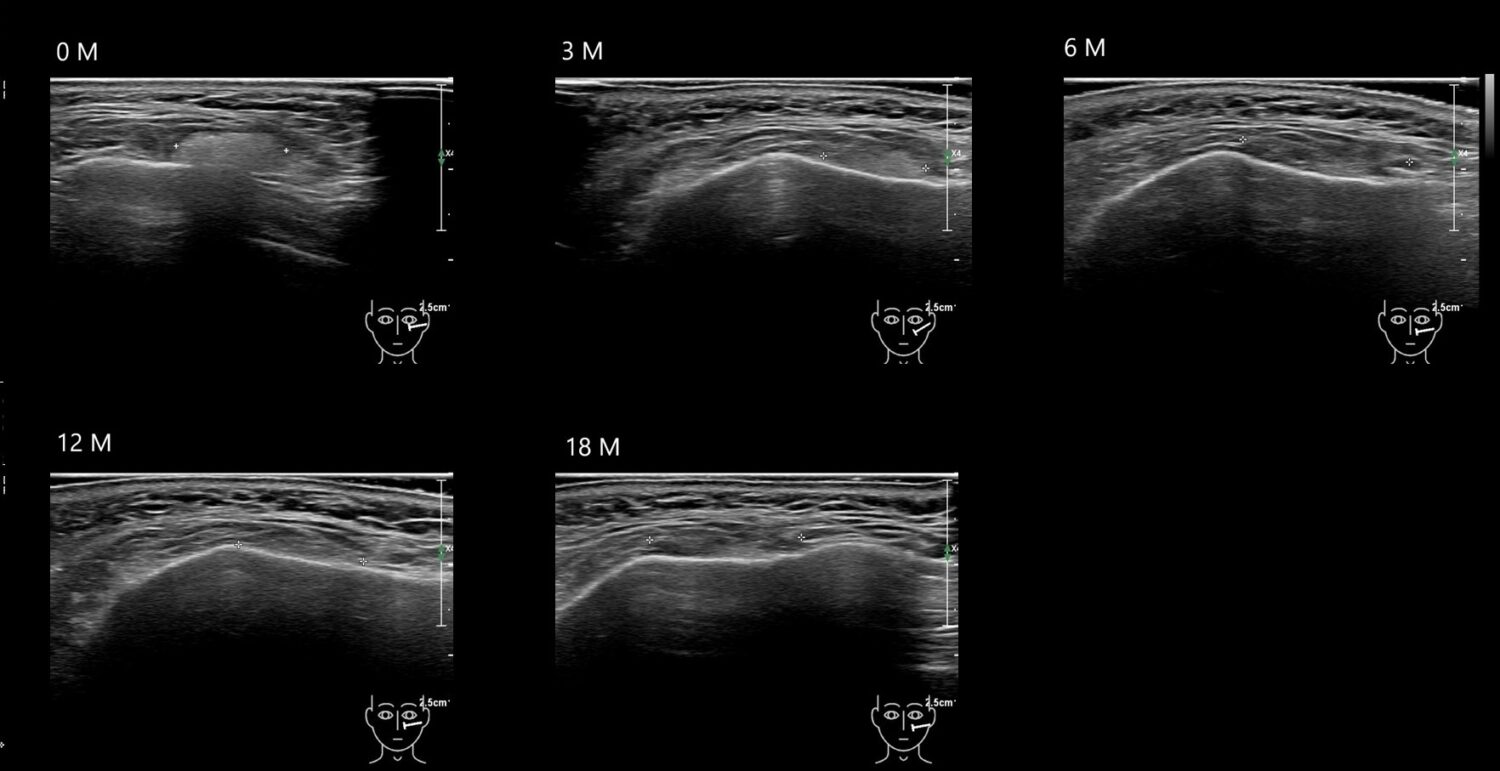

Fillers

Draw in the second image below where the fillers are located. To check if your answer is correct, swipe the first image to the right.